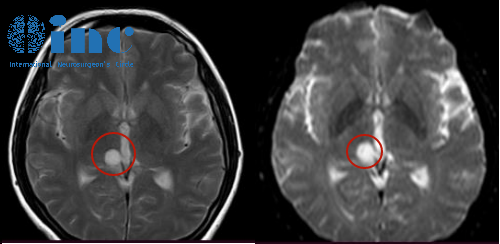

[案例] 開顱術后“零并發(fā)癥”,INC巴教授丘腦膠質瘤順利手術紀實

開顱術后“零并發(fā)癥”,INC巴教授丘腦膠質瘤順利手術紀實